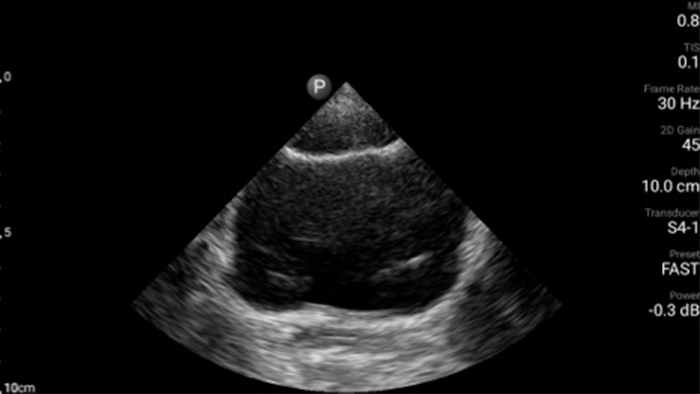

Respond fast with whole-body imagery

Lumify can help you assess patients from head to toe, whether it’s plantar fasciitis, tendonitis or bursitis in the patellar tendon, or even shoulder instability in the rotator cuff.

Lumify C5-2 broadband curved array transducer

• 5 to 2 MHz extended operating frequency range • 50mm radius of curvature • 2D, color Doppler, M-mode, advanced XRES and multivariate harmonic imaging, SonoCT • High-resolution imaging for deeper applications: abdominal, gall bladder, OB/GYN and lung imaging preset optimizations